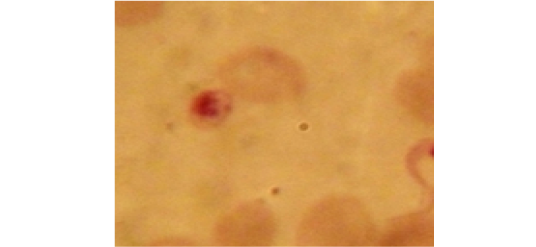

Showing intermediate form of T. evansi in examined camel (x 1000).